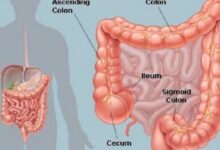

تُعرف الأمعاء الغليظة (بالإنجليزية: Large Intestine) بالقولون (بالإنجليزية: Colon)، ويُعدّ الأعور (بالإنجليزية: Cecum) أول أجزاء القولون، وهو الجزء الذي يرتبط باللفائفيّ (بالإنجليزية: Ileum) الذي يُمثّل آخر أجزاء الأمعاء الدقيقة، ويمكن القول إنّ القولون يُقسم إلى أربعة أجزاء رئيسية، وهي: القولون الصاعد (بالإنجليزية: Ascending Colon) الذي يوجد في الجزء الأيمن من البطن، والقولون المستعرض (بالإنجليزية: Transverse Colon) الذي يقطع البطن، والقولون النازل (بالإنجليزية: Descending Colon) الذي يمثل الجزء الأيسر من البطن، والقولون السينيّ (بالإنجليزية: Sigmoid colon) الذي يقع قبل المستقيم (بالإنجليزية: Rectum) تماماً. وتكمن وظيفة القولون في تصنيع البراز وإنتاجه، وذلك بسحب الماء، والأملاح، وبعض العناصر الغذائية، ومن الجدير بالذكر أنّ هناك مليارات البكتيريا الموجودة في القولون والتي تظلّ في مستوياتٍ تُبقيها متوازنة مع وضع الجسم وحاجته، وتُبطّن القولون مجموعة من العضلات التي تدفع البراز المتكوّن إلى الأجزاء السفلى.[١]